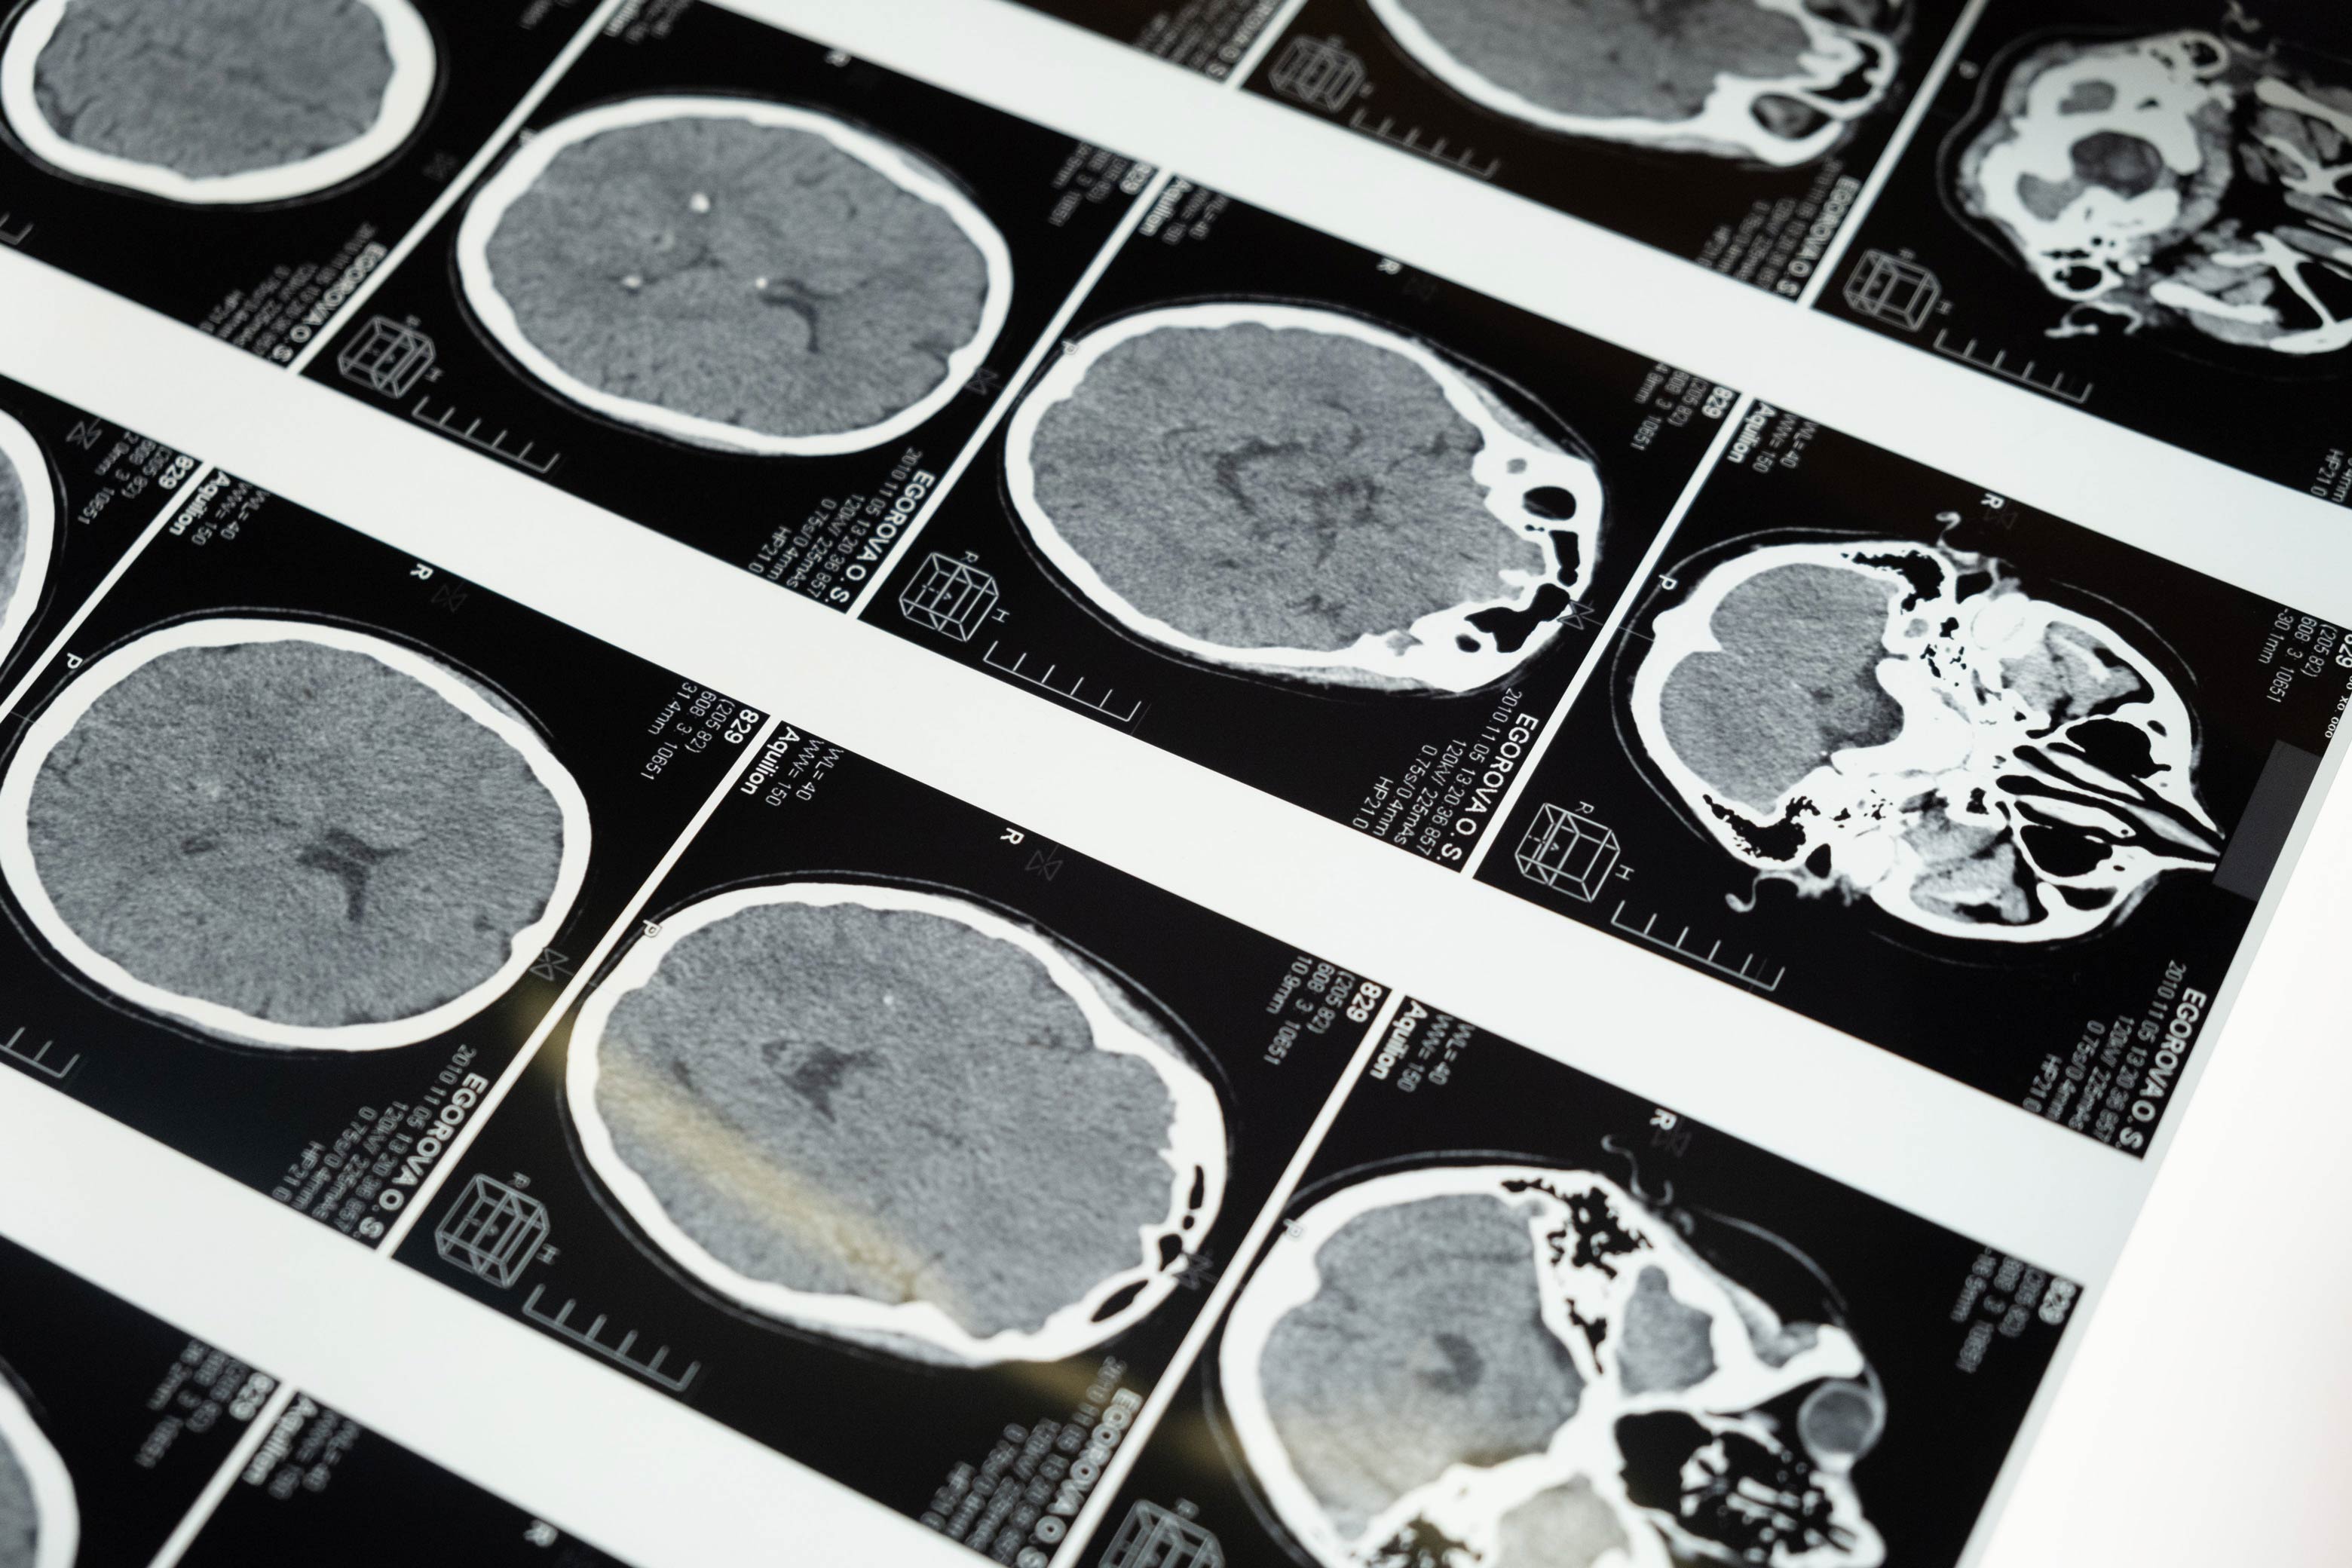

La investigación en neurociencia muestra que el cerebro adulto puede mejorar, no solo mantenerse. Intervenciones desde los 35 años han mostrado resultados positivos en función cognitiva. Con evaluación y estrategias personalizadas, estudios indican que es posible mejorar áreas cognitivas específicas conforme avanzas en edad, mientras se trabaja preventivamente en factores de riesgo. También, la evidencia científica actual sugiere que el deterioro cognitivo no necesariamente tiene que ser parte del envejecimiento, ya que diversos factores asociados pueden ser modificables mediante atención especializada. La consulta identifica factores que pueden trabajarse ahora para beneficio a largo plazo: